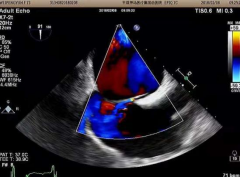

3、經(jīng)食道超聲心動圖及右心聲學(xué)造影

經(jīng)食道超聲心動圖用于精準(zhǔn)評價(jià)心臟內(nèi)血栓、卵圓孔未閉的類型及大小、心臟瓣膜損傷、感染性心內(nèi)膜炎等,也便于進(jìn)行心臟手術(shù)中的超聲監(jiān)測與評價(jià),科室近年來在經(jīng)食道超聲心動圖檢查及診斷上積累了豐富的經(jīng)驗(yàn)。

右心聲學(xué)造影可進(jìn)一步提高卵圓孔未閉、房間隔缺損、肺動靜脈瘺、永存左上腔靜脈等異常的超聲檢測率,尤其是不明原因的偏頭痛的病因篩查,科室開展右心聲學(xué)造影數(shù)百例,為偏頭痛的患者查找出了病因,為臨床治療提供了可靠的診斷依據(jù)。